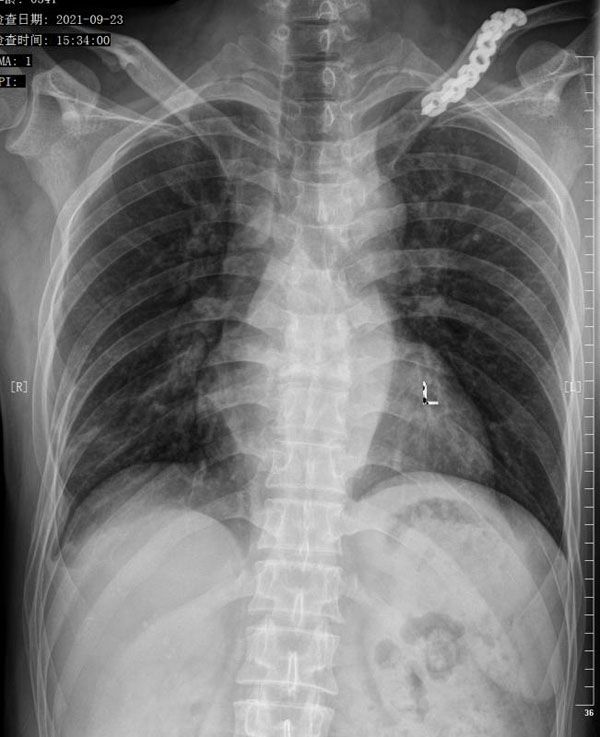

手术顺利,术后1周,樊先生便可下床行走,胸背部疼痛明显缓解,无神经损伤症状,复查X片提示内固定位置好。术后2周恢复良好,拆线出院。术后1月,复查胸背部无明显不适,复查血沉均在正常范围,樊先生感叹道:“我都没想到我能恢复这么快!”12月6号,樊先生和家属特地送来两面锦旗,表达对脊柱外科许立新主任团队的感激之情。